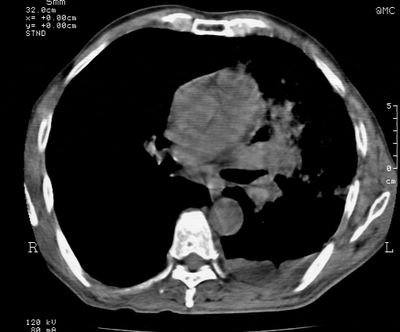

标题: CT24000:M65,胸痛,胸闷月余,既往慢支,肺气肿,肺心病 [打印本页]

标题: CT24000:M65,胸痛,胸闷月余,既往慢支,肺气肿,肺心病

左肺门肿块,相应支气管闭塞,左肺上叶、舌叶大片及散在高密度影,部分呈不张改变,两肺纹粗乱,左侧胸腔积液。考虑左侧中央型肺癌伴阻塞性改变。

左肺门见巨大软组织肿块影,直径约--,境界清,左上肺叶支气管变窄,左上肺舌叶见大片状密实影,余肺纹理增多、紊乱、纤细、部分网格状,两肺透亮度增高,纵隔内见增大多发淋巴结影,心影略左偏,左侧少量胸腔积液。

左侧中央型肺癌伴左上肺舌叶不张、纵隔淋巴结转移,左侧少量胸腔积液。